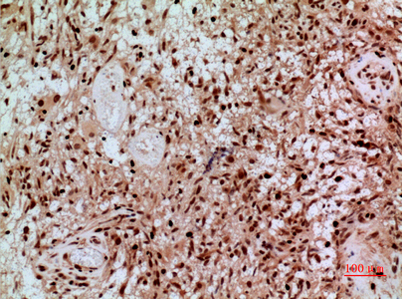

Product name: SAMHD1 rabbit pAb

Dilutions: Western Blot: 1/500 - 1/2000. IHC-p: 1/100-1/300. ELISA: 1/20000. Not yet tested in other applications.

Immunogen: The antiserum was produced against synthesized peptide derived from the Internal region of human SAMHD1. AA range:431-480